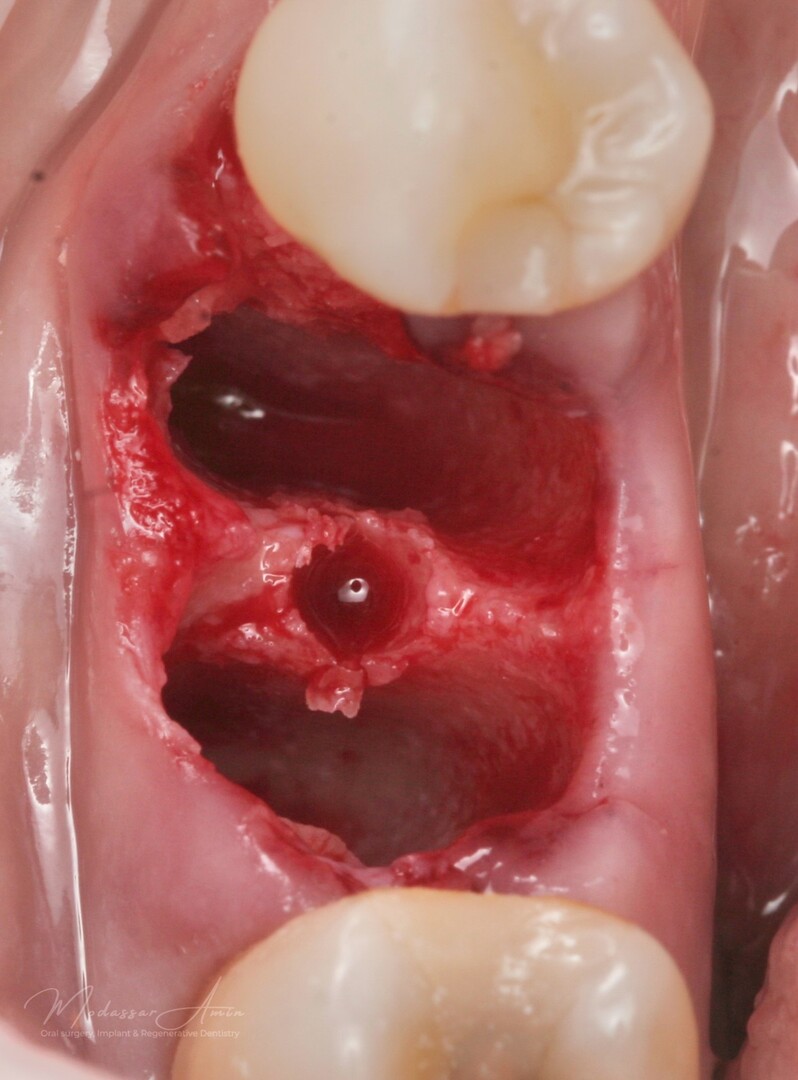

Pasienten presenterte med tann 46 som ikke kunne bevares grunnet en dyptgående infraksjon inn i furkasjonen. Forholdene lå til rette for en immediate implantatbehandling. Ved hjelp av Versah osseodensifikasjonsbor ble det interradikulære beinet ekspandert på en skånsom og forutsigbar måte, noe som ga høy primærstabilitet (>40 Ncm) til tross for en lokal bendefekt apikalt mesialt etter kronisk apikal periodontitt. Den gode stabiliteten muliggjorde bruk av SSA (Sealing Socket Abutment) for forsegling. På grunn av tynn bløtvevsfenotype bukkalt ble behandlingen supplert med bindevevstransplantat (CTG):

Starten på ekspansjon

Versah bor 2.3

Septum ekspandert